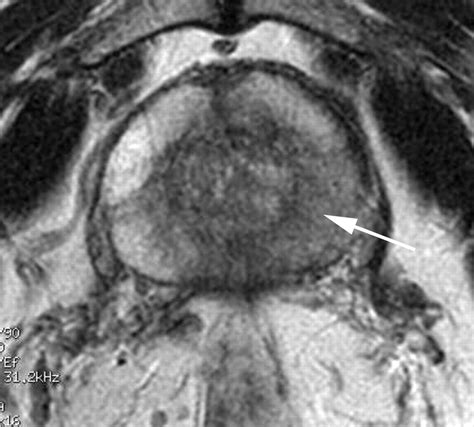

• T2-weighted imaging: Provides high-resolution anatomical images, allowing the radiologist to see the shape and size of the prostate clearly.

After your MRI of prostate is completed, the images are analyzed by a specialized radiologist. They use a standardized reporting system known as PI-RADS (Prostate Imaging-Reporting and Data System). This system assigns a score from 1 to 5 to any suspicious areas identified:

• PI-RADS 4: Clinically significant cancer is likely.

• PI-RADS 5: Clinically significant cancer is highly likely.